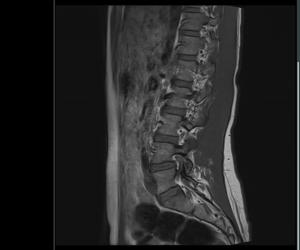

Sofand Skrevet 10. mars 2019 Forfatter Skrevet 10. mars 2019 Bildet er ikke det tydeligste, men ser ut som en gammel prolaps mellom L4 og L5. Tusen takk for svar! Sier disse bildene noe mer kanskje?

Sofand Skrevet 10. mars 2019 Forfatter Skrevet 10. mars 2019 er dy bekymret for noe som dette er det noe du bør undersøke os en lege, ikke på internett. Jeg er i kontakt med lege, venter på svar ang. MR-undersøkelsen. Ville se om noen med erfaring kunne tyde bildet, uten at jeg konkluderer med noe på bakgrunn av det :-)